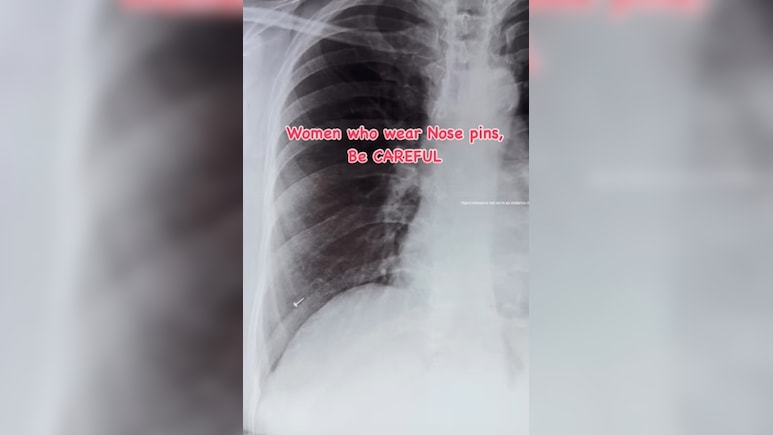

Nose Pin In Lungs: आपने अक्सर व्यक्ति के पेट में किसी ना किस चीज के फंसे होने की खबरों को पढ़ा होगा. ऐसा ही एक और मामला सामने आया है. इसमें एक महिला के फेफड़े में नाक की पिन गहराई तक फंसी मिली. हैरानी की बात यह रही कि मरीज में किसी तरह के साफ लक्षण दिखाई नहीं दे रहे थे. न खांसी, न तेज दर्द और न ही सांस लेने में परेशानी. जांच के दौरान जब एक्स-रे और स्कैन किया गया, तब फेफड़ों में नोजपिन के फंसे होने की बात पता चली.

ऐसे में डॉक्टर्स का कहना है कि कई बार शरीर को अंदर कोई चीज घुसी होती है लेकिन कोई दिक्कत नहीं होती और समय के साथ यह एक गंभीर समस्या बन सकती है. फेफड़ों में इस तरह की चीजों के फंसने से इंफेक्शन, सूजन या सांस लेने में दिक्कत आदि समस्याओं का सामना करना पडता है. इसलिए इसे हल्के में नहीं लेना चाहिए और कपड़े आदि उतारते और पहनते समय ध्यान रखना चाहिए.